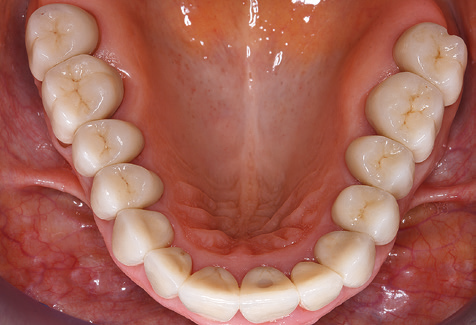

Eine 52-jährige Patientin stellte sich nach Zahnverlust im 3. Quadranten erstmals 2004 vor. Sie hatte den Wunsch nach einer prothetischen Neuversorgung. Im Rahmen der parodontologischen und radiologischen Diagnostik zeigte sich ein ausgeprägter parodontologischer Behandlungsbedarf. Die Zähne 48, 28, 27 zeigten zudem eine infauste Prognose und wurden entfernt (Abb. 1). Nach der erfolgreich abgeschlossenen systematischen PARTherapie wurde eine festsitzende implantatprothetische Versorgung mit Insertion von fünf Implantaten in Regio 35, 36, 37 und 46, 47 durchgeführt. Die prothetische Versorgung der natürlichen Zähne erfolgte mit verblendeten Zirkonoxidkeramikkronen, die Implantate wurden mit zweiteiligen individuellen Zirkonoxidabutments und ebenfalls verblendeten Kronen aus einer Zirkonoxidkeramik versorgt (Cercon base colored, Dentsply Sirona Lab). Die definitive Insertion der prothetischen Versorgung erfolgte im Jahr 2005.

Aufgrund der bestehenden parodontalen Vorerkrankung erfolgte die unterstützende Parodontaltherapie (UPT) in den ersten Jahren in einem DreiMonatsIntervall. Dabei zeigte die Patientin eine hohe Motivation und gute Compliance. Bei den jährlich erhobenen Sondierungsbefunden zeigten sich stabile parodontale Verhältnisse mit einem BOPIndex unter fünf Prozent. Aufgrund der stabilen parodontalen Situation und der guten Mitarbeit der Patientin wurde ab dem sechsten Jahr der prothetischen Funktionsphase das Recallintervall auf halbjährlich umgestellt. Auch mit diesem veränderten Recallintervall zeigten sich bei der jeweils jährlichen Aufnahme des Parodontalstatus stabile parodontale Verhältnisse, ohne Zunahme der Sondierungstiefen und einem BOPIndex unter fünf Prozent (Abb. 2a und b).

Im Rahmen der ZehnJahresKontrolle zeigten sich keine Hinweise auf einen fortschreitenden parodontalen Attachmentverlust oder einen periimplantären Knochenverlust (Abb. 3).

Für den klinischen Langzeiterfolg des parodontal kompromittierten Patienten ist die standardisierte und regelmäßige risikoadaptierte Betreuung im Rahmen der UPT der zentrale Baustein des Behandlungserfolgs. Dies gilt in besonderer Weise für Patienten, die nach erfolgreich abgeschlossener parodontaler Sanierung mit Implantaten versorgt wurden (Abb. 11a und b).